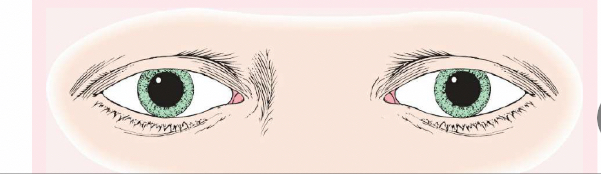

Pseudostrabismus

Normal in young children, the pupils will appear at the inner canthus (due to the epicanthic fold).

Strabismus (or Tropia)

A constant malalignment of the eye axis, is defined according to the direction toward which the eye drifts and may cause amblyopia.

Esotropia

(eye turns inward).

Exotropia

(eye turns outward).

Phoria (Mild Weakness)

Noticeable only with the cover test, is less likely to cause amblyopia than strabismus.

Esophoria

is an inward drift and

exophoria

an outward drift of the eye.